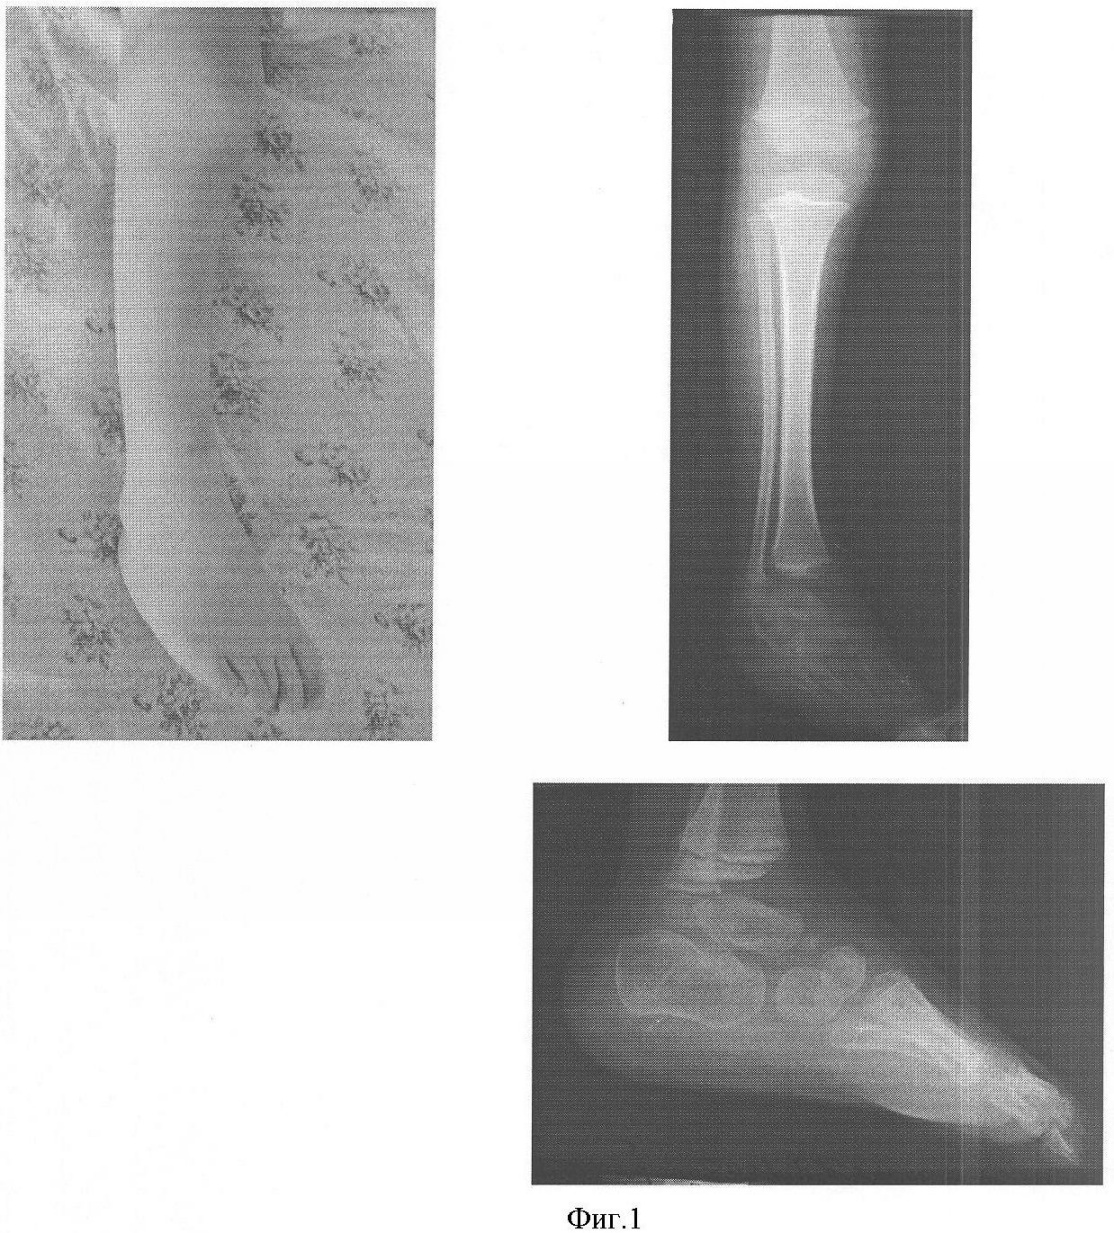

На фиг.1 представлены фото и рентгенограмма конечности ребенка 3 лет до оперативного лечения.